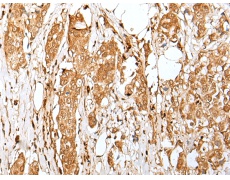

IHC positive control: |

Human tonsil and human breast cancer |

IHC Recommend dilution: |

30-150 |